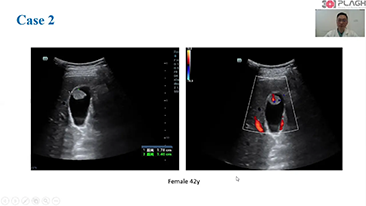

Aparaty ultrasonograficzne z serii Resona, dzi?ki szerokiej gamie za pomoc? wszechstronnych sond do r√≥?nych zastosowaŇĄ i wydajnych narz?dzi do zastosowaŇĄ klinicznych, pomagaj? U?ytkownikom stawia? dok?adniejsz? i efektywniejsz? diagnoz? oraz ocenia? wyniki.

Produkty do obrazowania ogólnego